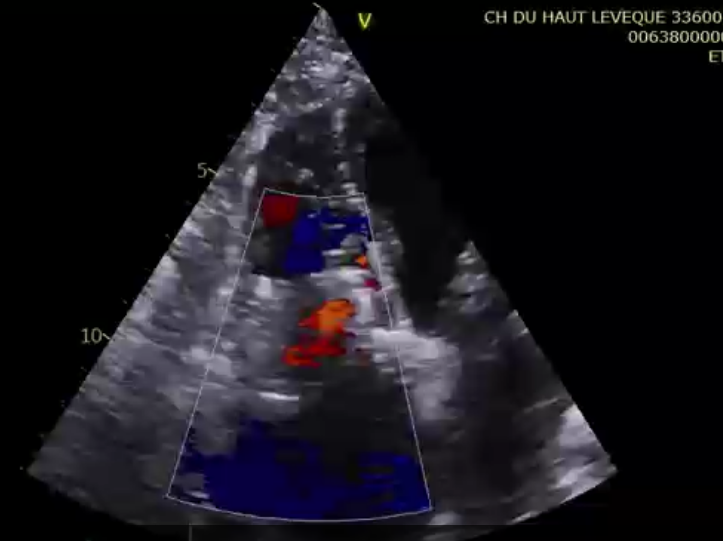

術后超聲提示微量瓣周漏

第二名患者是一位79歲的女性,術前TTE診斷TR等級4+,既往有高血壓、腎功能不全、肺動脈高壓的病史。術者在擁有第一臺手術的經驗后,在TEE和DSA的引導下非常順利地完成瓣膜的釋放,術后瓣膜形態穩定,TEE提示即刻反流0+。患者術后七天TTE復查提示無明顯三尖瓣反流,瓣膜整體形態非常穩定。